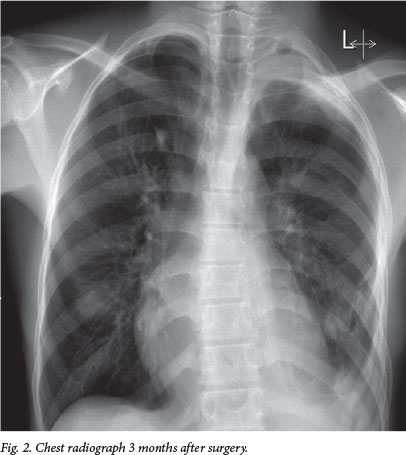

The underlying lung appeared normal and eventually re-expanded completely. The patient's postoperative course was uneventful, and he was discharged a week after surgery. He is due to be followed up in the Department of Oncology at IALCH and will require radiological surveillance. Fig. 2 shows a chest radiograph 3 months after surgery. Histological examination of the resected 3.3 kg specimen confirmed a desmoid tumour.